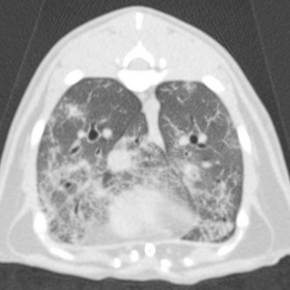

Diagnostic imaging showing pet lungs

CT has revolutionised respiratory diagnostics. By eliminating superimposition, it reveals fine detail invisible on radiographs and provides three-dimensional assessment of the thorax.

• Diffuse interstitial or subtle parenchymal disease.

• Pulmonary nodules or masses not visible radiographically.

• Bronchiectasis, bullae, and small airway disease.

• Vascular or mediastinal abnormalities, including pulmonary thromboembolism.

In patients with suspected neoplasia, inflammatory lung disease, or complex congenital anomalies, CT offers a definitive diagnosis and detailed disease mapping. Modern CT protocols enable rapid image acquisition under light sedation, minimising anaesthetic time and improving safety, even for compromised cardiac patients.